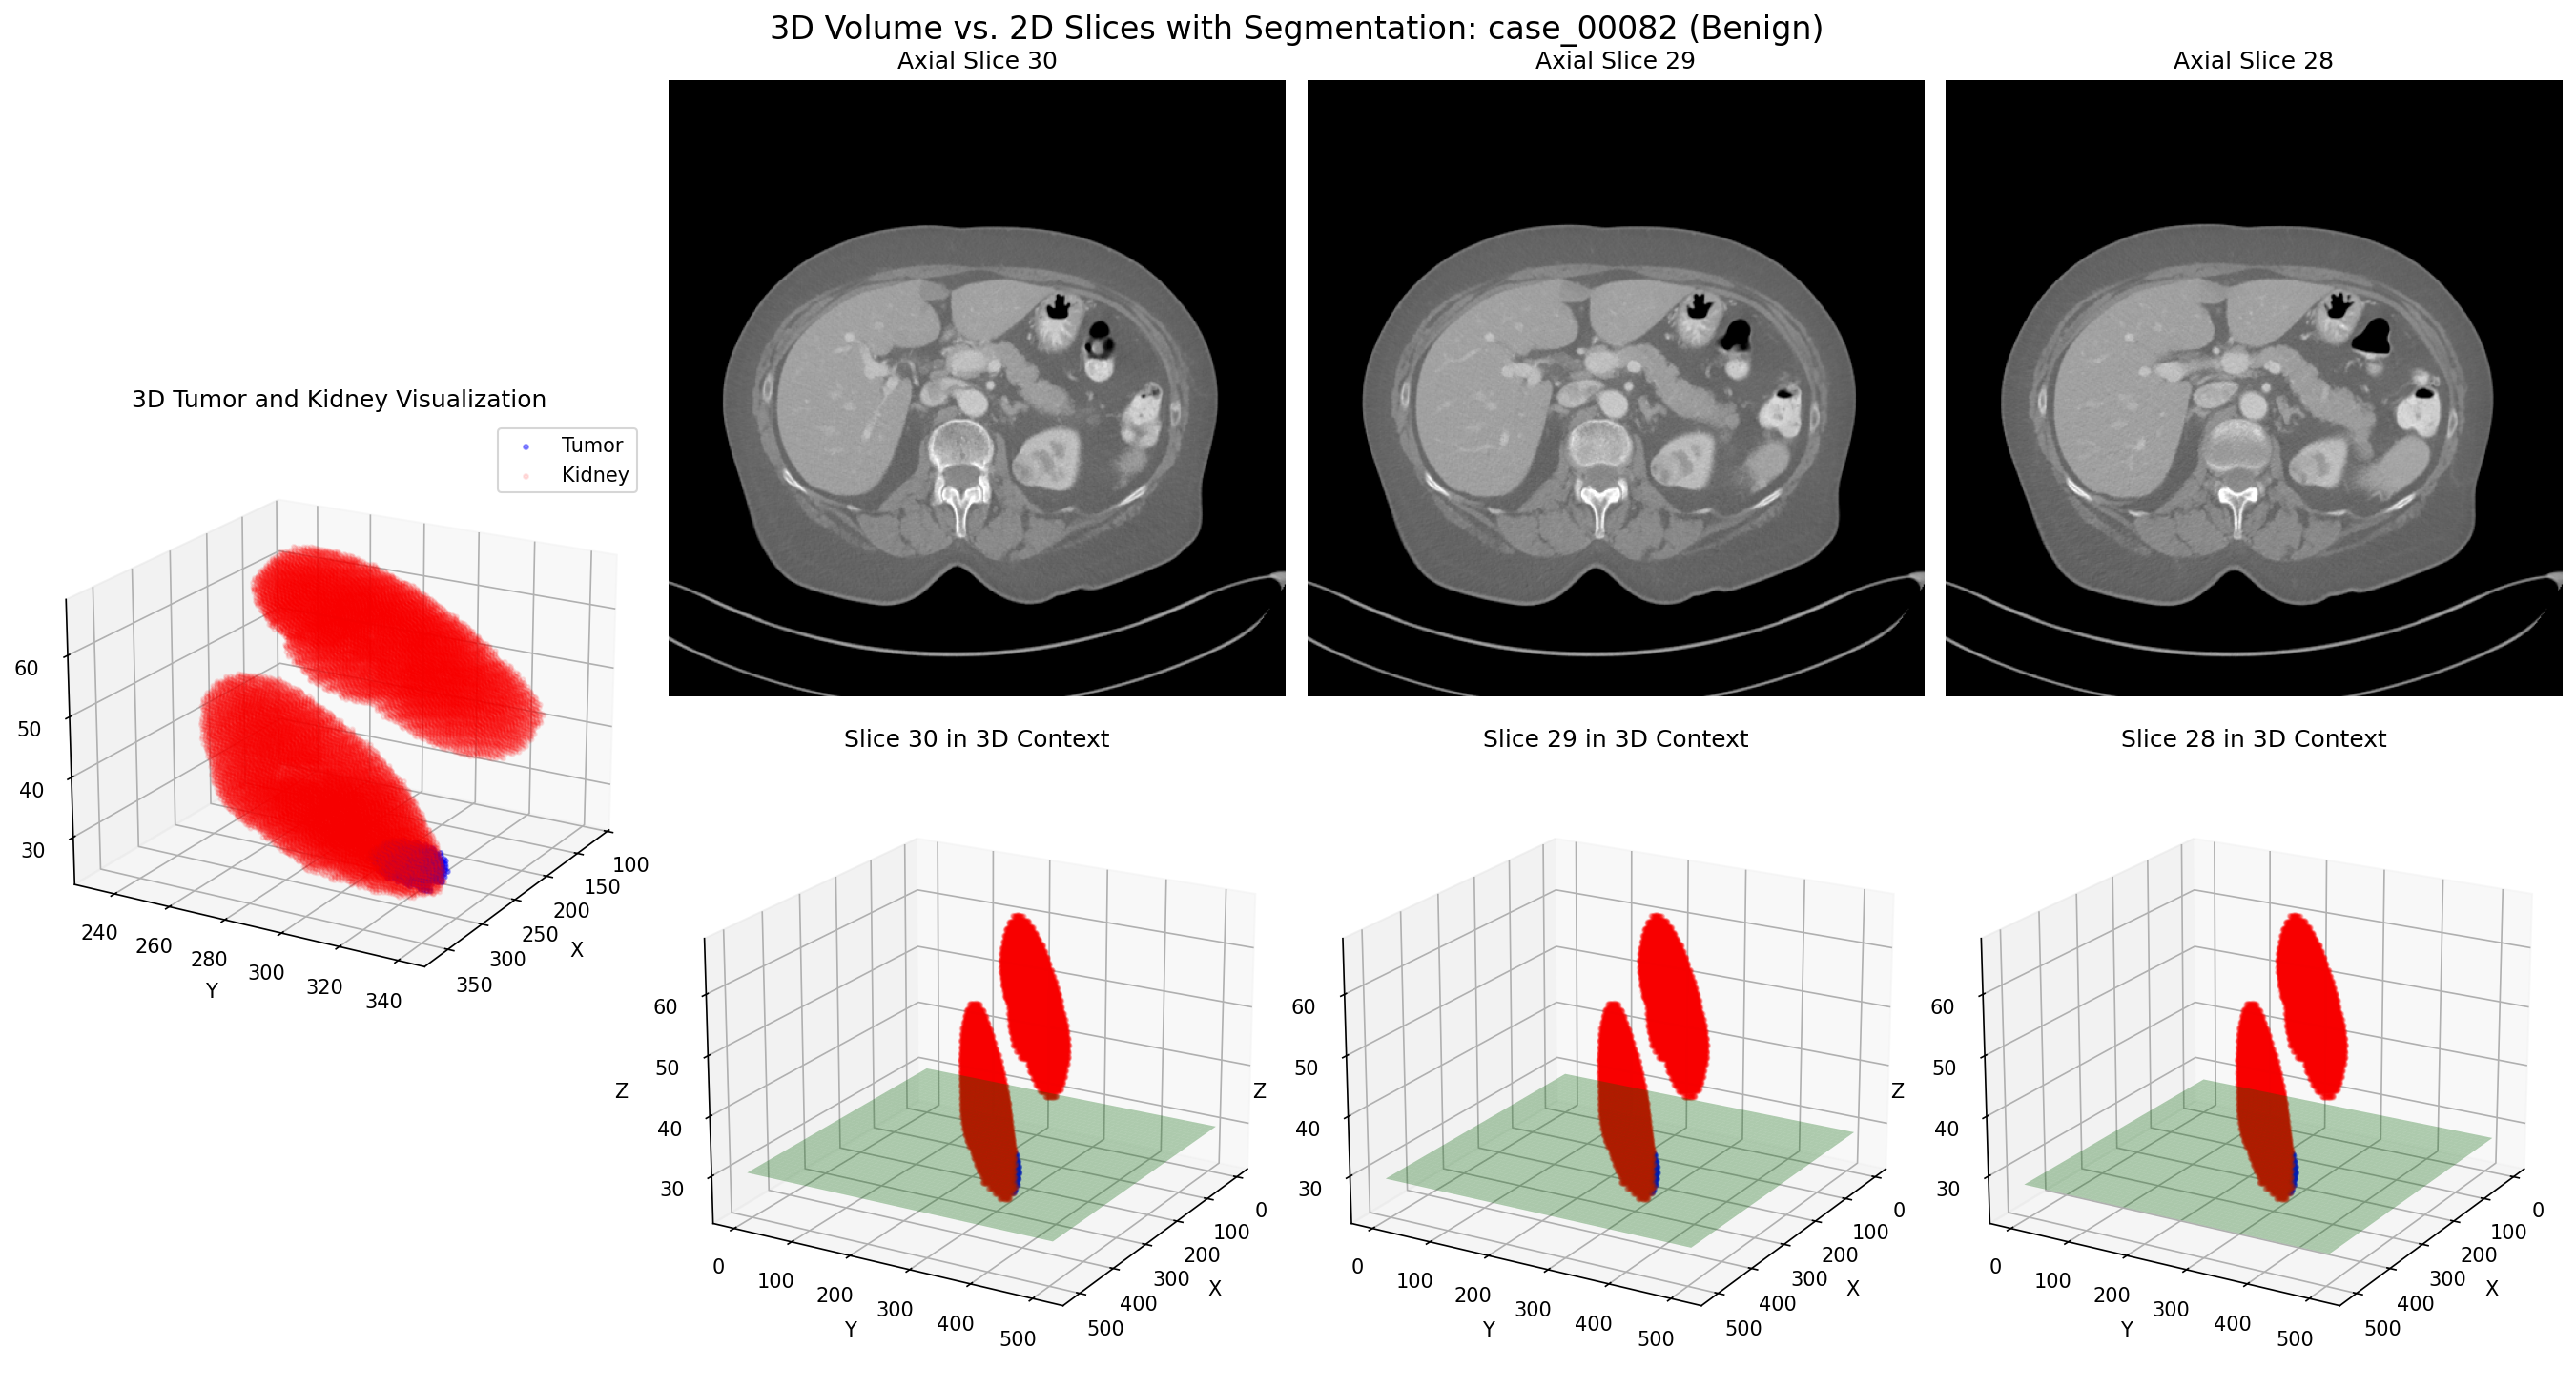

Distinguishing Benign vs. Malignant in 3D

Side-by-side comparison of 3D representations of malignant (left) and benign (right) kidney tumors, highlighting morphological differences

The comparison above highlights the differences between malignant (left) and benign (right) kidney tumors in 3D. Benign tumors often display more regular, well-defined boundaries and more uniform internal composition, while malignant tumors typically show irregular borders, heterogeneous internal structure, and may invade surrounding tissues.